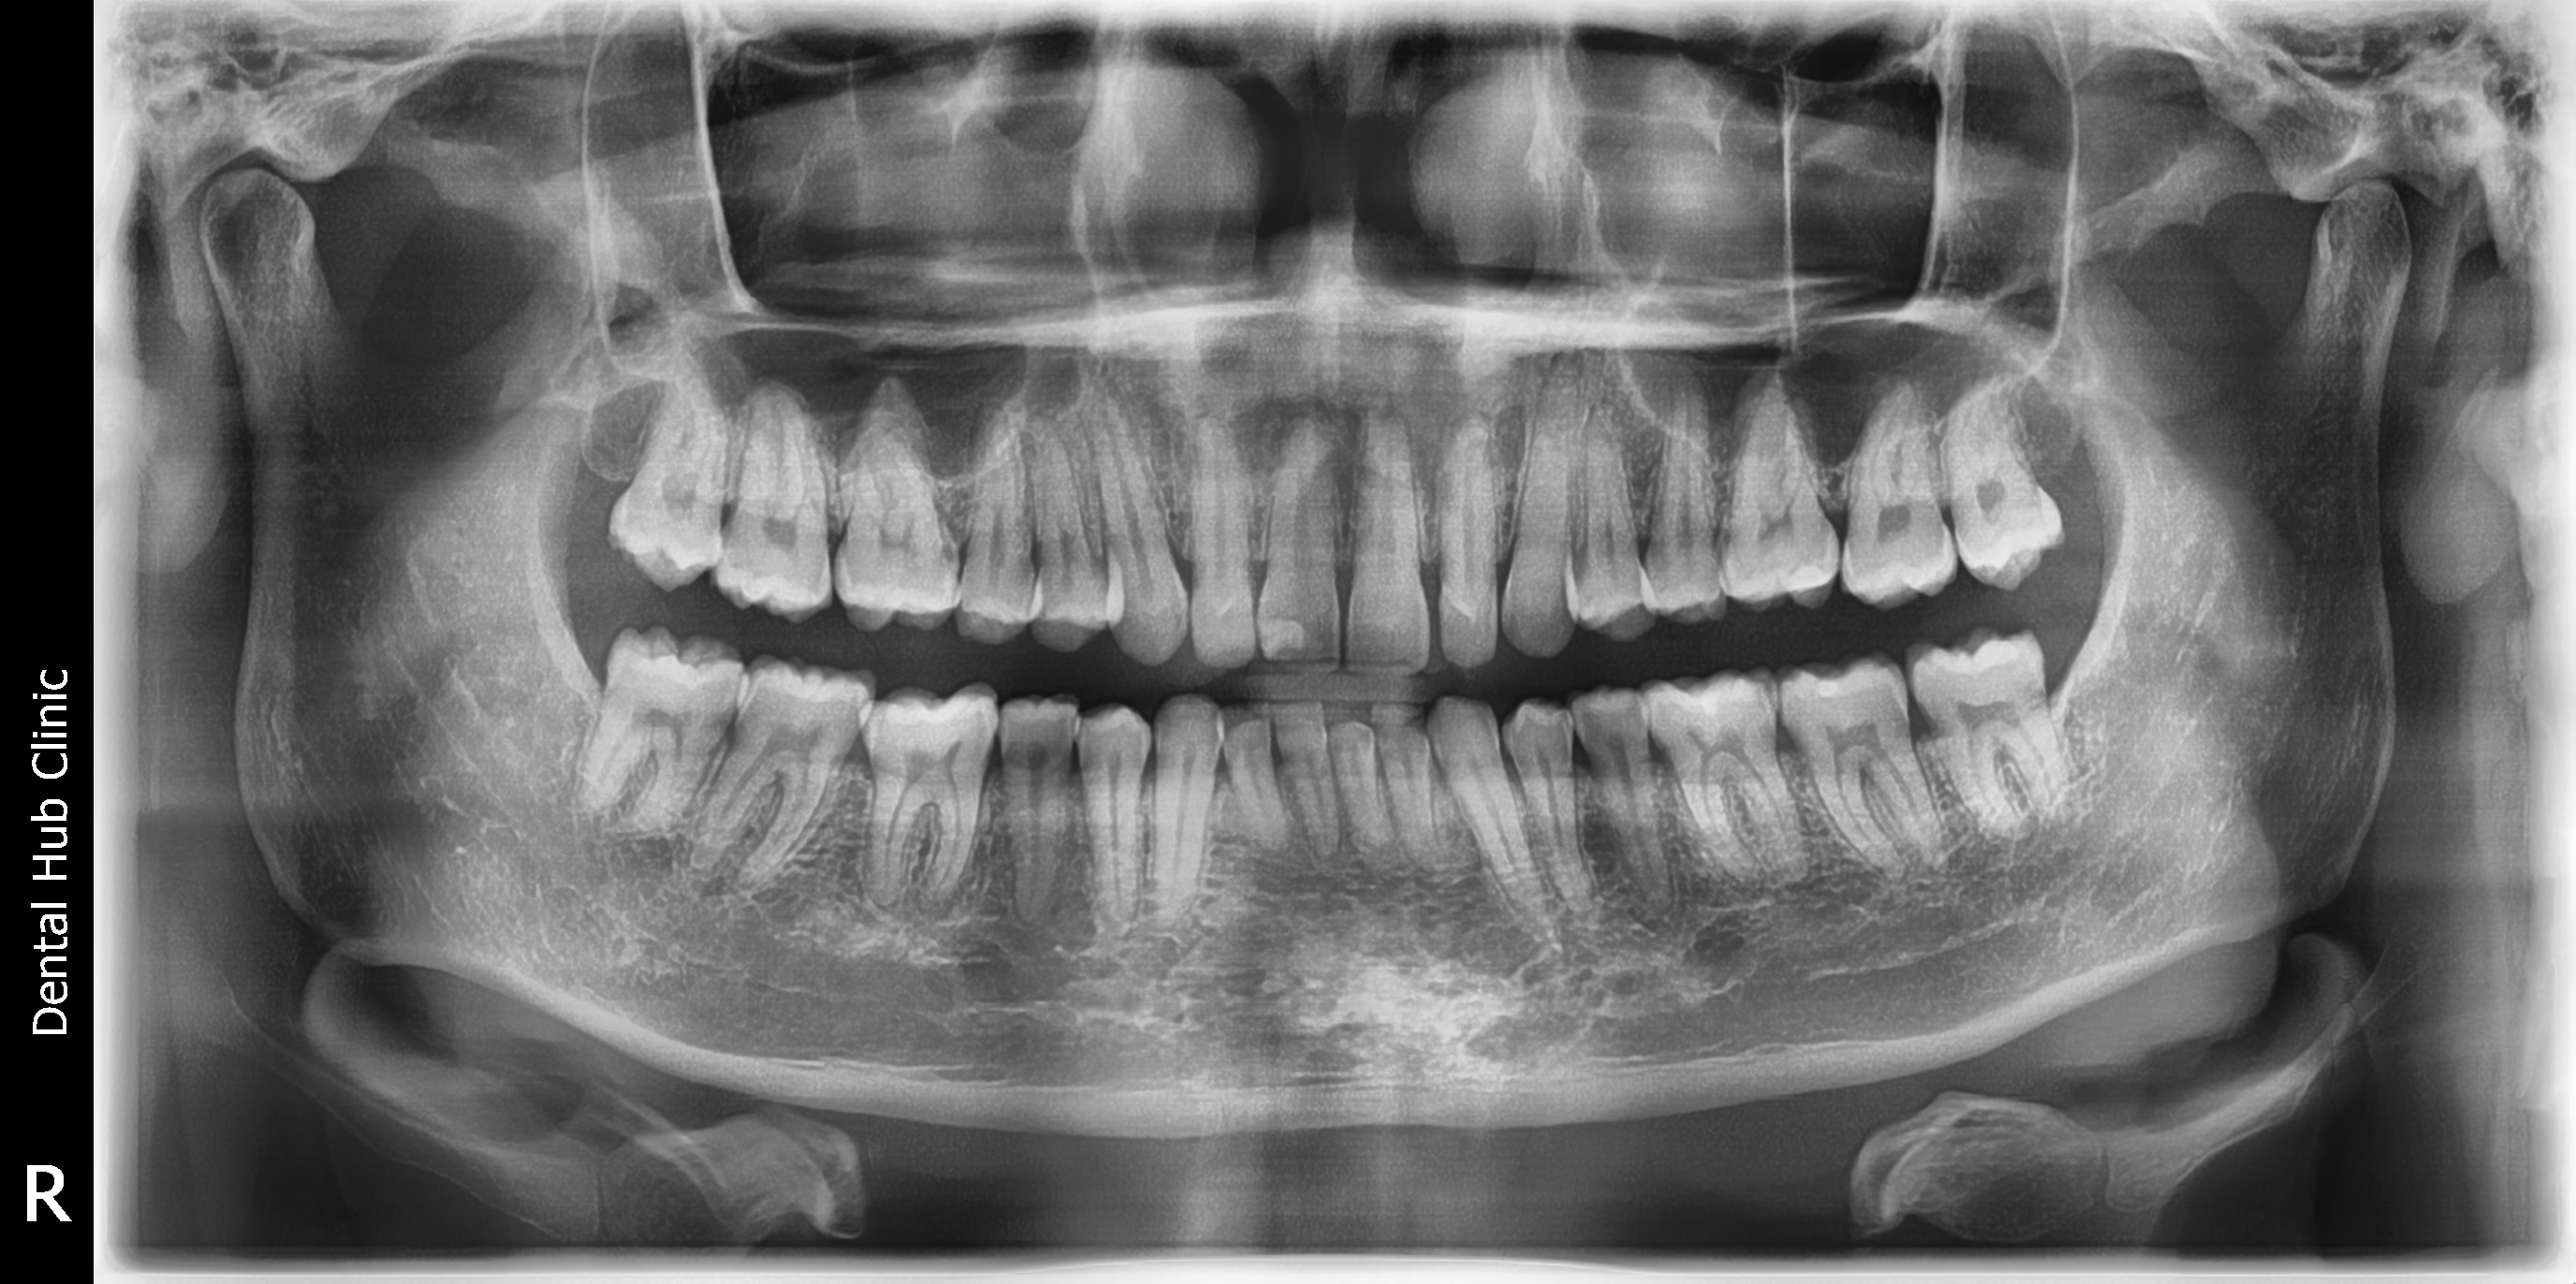

- Joseph

- Ducay

- 08/10/24 OP 10/05/24 #18 #28 w/ peducle flap due to #28 is near to sinus w/ chromic gut suture 10/19/24 ff.check up

- joseph_manual.jpg